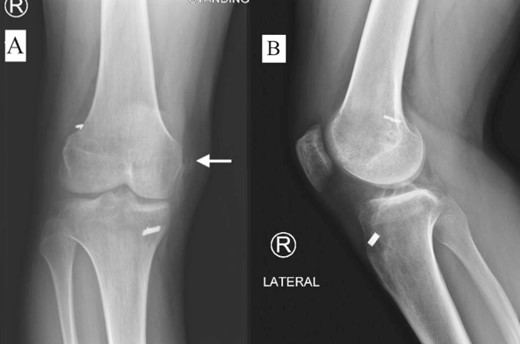

A 23-year-old male veterinarian presented to our out-patient department postright ACL reconstruction with hamstring autograft, PHMM tear by all-inside repair via sMCL pie-crusting technique, and lateral extra-articular tenodesis (modified Lemaire) in June 2023. A preoperative plain radiograph of the right knee revealed no evidence of HO (Fig. 1). No evidence of heterotopic ossification was detected in the right knee on plain radiographs taken 2 weeks postsurgery. (Fig. 2). Five months postsurgery, plain radiographs revealed new bone formation at the medial femoral condyle, precisely where the sMCL femoral origin was located (Fig. 3). The patient was asymptomatic and continued with rehabilitation. Seven months after the surgery, the patient started to complain of pain and clicking sensations when the right knee was flexed beyond an angle of 130°. Magnetic resonance imaging revealed consolidation of the newly formed bone, leading to a diagnosis of HO post-sMCL pie-crusting (Fig. 4). Nine months following surgery, the patient began to feel a bony mass on the medial side of the right knee. A plain radiograph and computed tomography (CT) scan revealed the complete formation of a bone island (Fig. 5). The past surgical history of this patient revealed that he had undergone left knee ACL reconstruction with hamstring autograft in December 2021, which failed and was complicated by a PHMM tear. The patient had presented to our facility for a revision. A revision ACL reconstruction was done using a bone-tendon-bone (BTB) autograft and PHMM tear all-inside repair via the sMCL pie-crusting technique in February 2022. A 2-year follow-up of the left knee, including physical examination and 3D-CT scans (Fig. 6), revealed no symptoms or signs of HO, although the same technique of sMCL pie-crusting was employed. Our patient suffered no head trauma during treatment. Past medical, drug, allergy, family, social histories, and reviews of systems were irrelevant to our case.

Plain radiograph of right knee AP (A) and lateral (B) 2 weeks postoperative showing no HO.